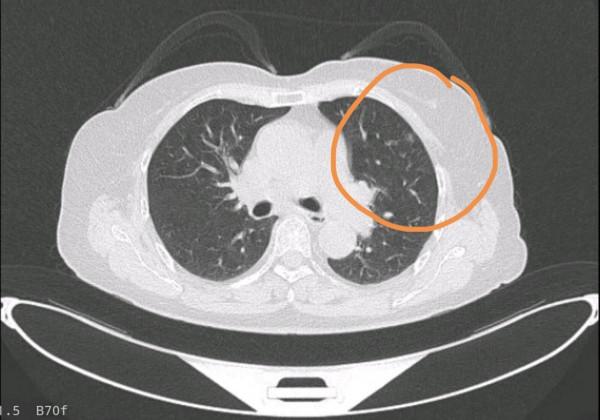

可是,當這一次體檢的報告出來後,劉醫生不淡定了,在父親的肺部CT上,能明顯看到有一個直徑在1.5cm左右的邊境不清晰的陰影,多年的臨床經驗讓劉醫生一下子就明白了,這是肺轉移癌,不過好在屬於早期,問題並不太大。

等到切除癌症灶的時候,王醫生停了下來,他先切了癌症灶的部分組織,準備到病理科化驗,因為在沒搞清楚癌症的基底時並不能直接切,很快病理科的診斷出來了,原來是原發性的小細胞肺癌,並不是結腸癌轉移肺癌。

王教授當機立斷,切除了劉父的部分肺葉。這次的手術危險係數其實比較大,患者年齡70多歲了,而且有曾經做過癌症手術的經歷,因此較為兇險,不過好在王教授技術嫻熟,僅用了一個小時便切除癌症灶。

劉醫生的父親為什麼突然患上肺癌?主刀醫生王教授切開劉父的肺葉後驚訝地發現,他肺部的淋巴結增生非常多,肺部血管很難找到與精準下刀。

而它肺部淋巴結增生的原因,就是粉塵吸入過多導致肺泡難以擴張,最終促使淋巴液分泌增加,淋巴功能亢進。久而久之就演變成了肺小細胞癌症。